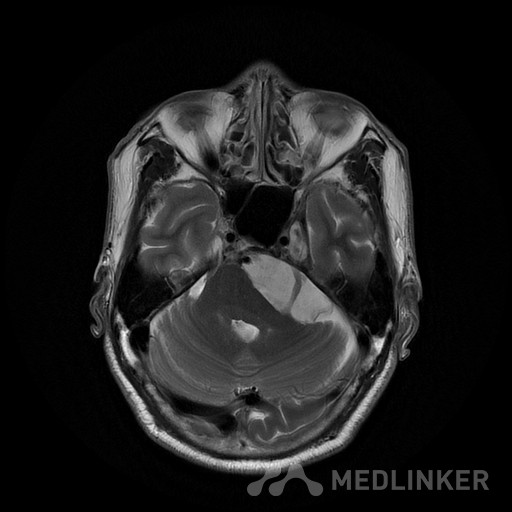

桥小脑区长T1长T2囊状病灶(如图),考虑表皮样囊肿还是蛛网膜囊

如图所示,左侧桥小脑区的囊状长T1长T2异常信号,增强扫描未见强化。考虑表皮样囊肿还是蛛网膜囊肿?